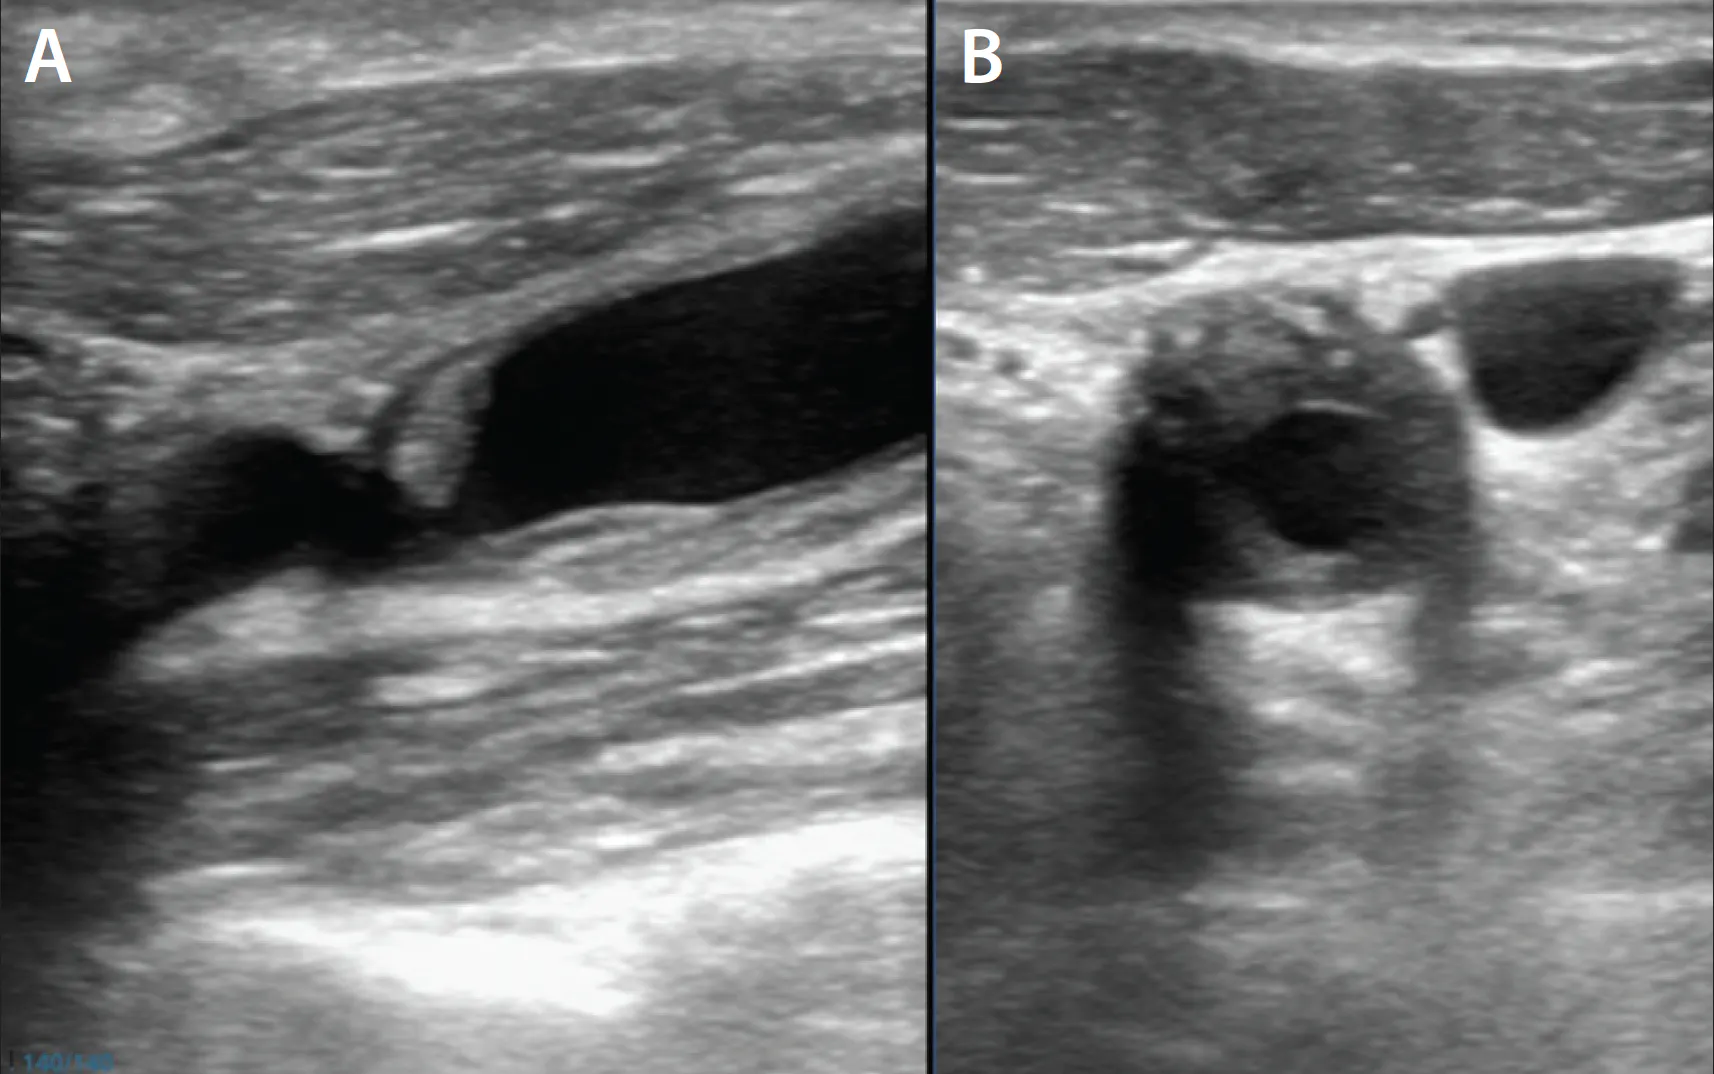

A middle-aged man with no significant past medical history presented to the emergency department with acute-onset aphasia upon waking up. On clinical examination, the patient had mild aphasia and was unable to answer orientation questions (National Institutes of Health Stroke Scale [NIHSS] 2). A CT scan of the patient’s head showed no intraparenchymal bleed or early ischemic changes. A left MCA dot sign was noted. CTA of the head and neck showed an M2 occlusion in the distal left MCA, as well as bilateral carotid disease with near-complete occlusion of the left proximal cervical carotid artery (Figure 1A-C). These findings were later confirmed by carotid duplex ultrasound, which revealed a PSV of 296.3 cm/s and EDV of 30.4 cm/s.

Figure 1. Axial CT of the head with a left MCA dot sign (A). Coronal CTA of the head showing M2 cutoff in the left distal MCA (B). CT perfusion demonstrating a mismatch between infarct core and penumbra (C). Axial T2-FLAIR MRI demonstrating the extent of infarction within the left MCA territory (D).

The patient was not deemed a candidate for intravenous thrombolysis, as he was outside the window of mechanical thrombectomy given the distal occlusion with low NIHSS. A secondary stroke workup included an unrevealing transthoracic echocardiogram. MRI of the brain showed a moderate infarct burden in the left MCA territory (Figure 1D). The etiology was thought to be large vessel atherosclerosis. The patient was loaded with antiplatelet medication (aspirin and clopidogrel) and a P2Y12 was checked to ensure responsiveness to clopidogrel.